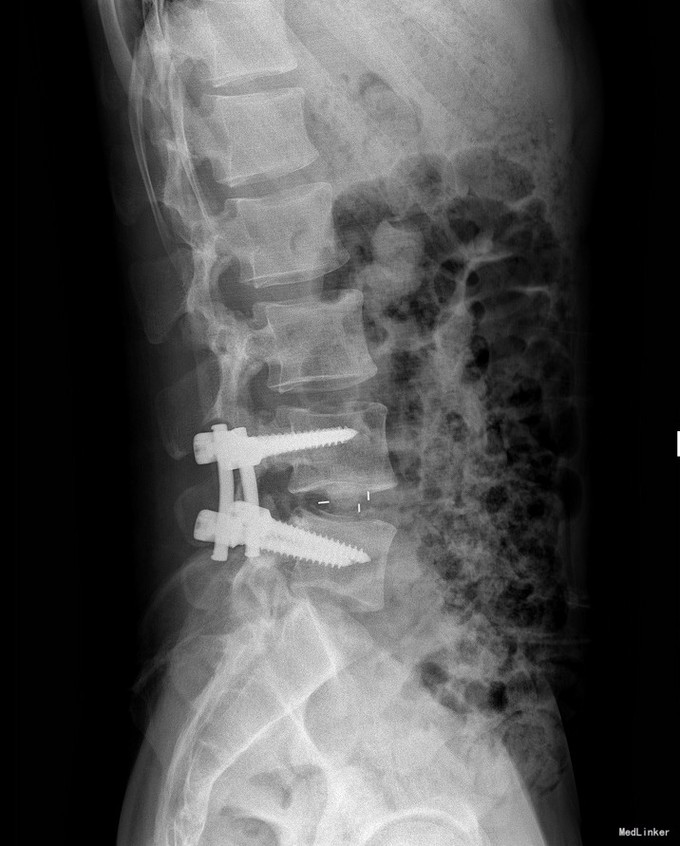

诊断 处理

腰椎椎管内占位 腰椎后路开窗减压+椎间融合+内固定术

随访 讨论

双下肢疼痛消失,生活自理